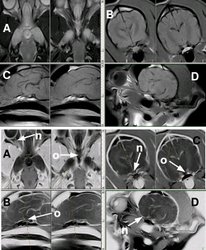

Detalle del quisma óptico de un gato (imagen de resonancia magnética)

Vía óptica. Cocker. Nervio óptico (n), quiasma óptico (o) Se muestran 4 secuencias de resonancia magnética, en positivo (las de arriba) y en negativo (las de abajo) A: SE T2 dorsal. B: SE T1 transversal. C: SE T1 sagital. D: SE T1 oblícuo, siguiendo la trayectoria del nervio óptico izquierdo, del cual se visualiza perfectamente su entrada por el agujero óptico del esfenoides.